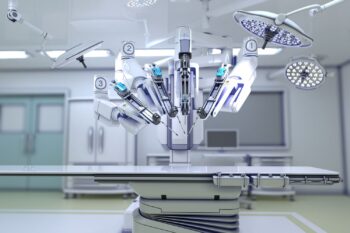

Robotic Joint Precision Technology Robotic joint precision technology in Nagpur At Asian Institute Of Advanced Surgeries in Nagpur, Dr. Abhishek Bhalotia, represents one of the most advanced developments in...

Robotic knee replacement in Nagpur Robotic knee replacement in Nagpur is an advanced orthopaedic surgical technique that uses robotic technology and computer-assisted planning to improve the precision of knee...

Robotic-assisted orthopedics (United SSH) Finding an experienced Robotic-assisted orthopedics (United SSH) Dr. Abhishek Bhalotia Orthopaedic Surgeon In Nagpur,practicing at Asian Institute Of Advanced Surgeries, It is essential for individuals...

Robotic-Assisted Orthopedics In Nagpur (United SSH) Robotic-assisted orthopedics In Nagpur(United SSH) is an advanced surgical technology that improves the accuracy and precision of joint replacement procedures. By combining robotic...